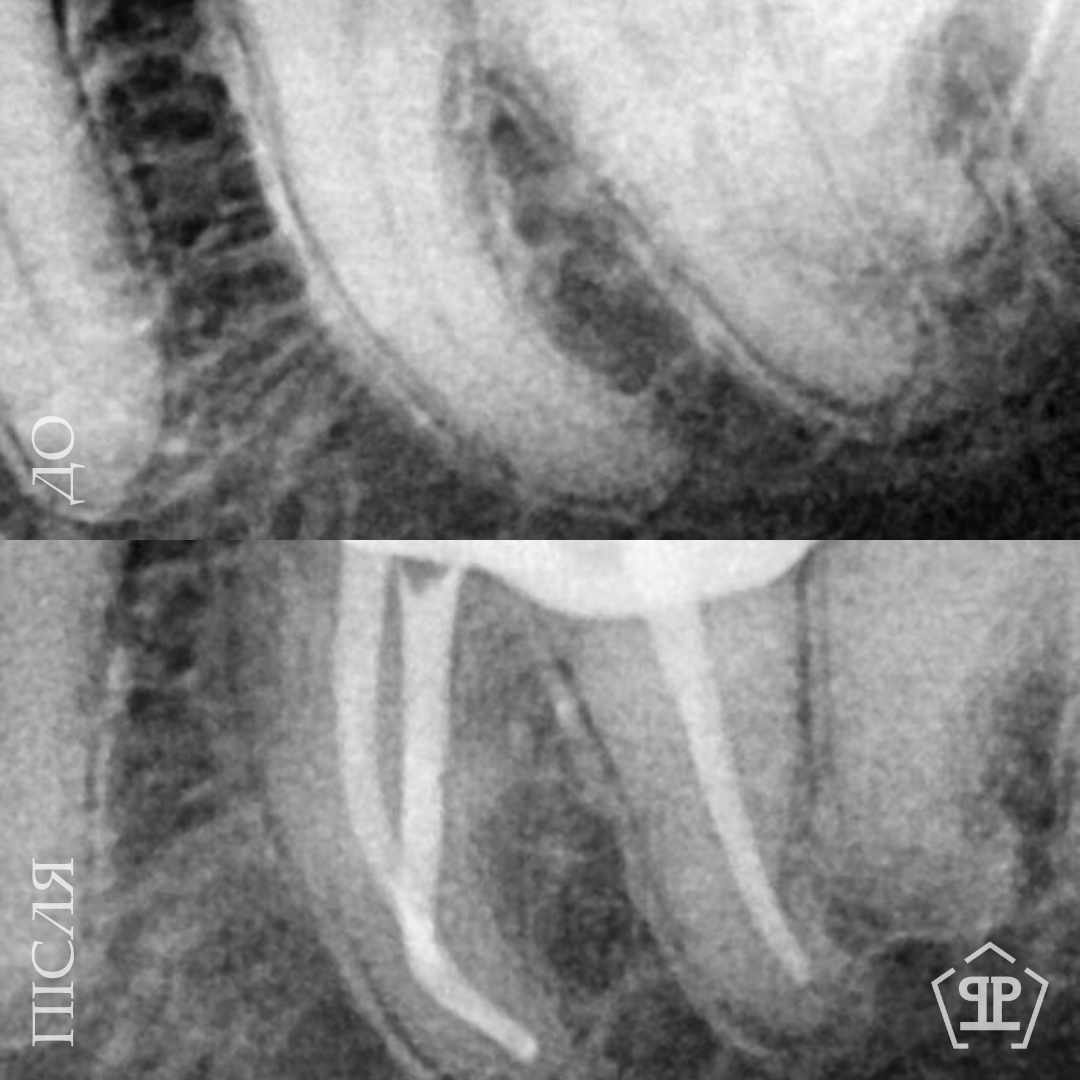

Перелечивание корневых каналов. Пациент обратился с симптомами, свидетельствующими о недостаточном предварительном лечении. Выполнены перечисления корневых каналов, тщательная очистка и повторная пломбировка для достижения полной герметичности и предотвращения рецидива воспаления.

Первичное лечение корневых каналов. Лечение пульпита, возникшего вследствие глубокого кариеса.